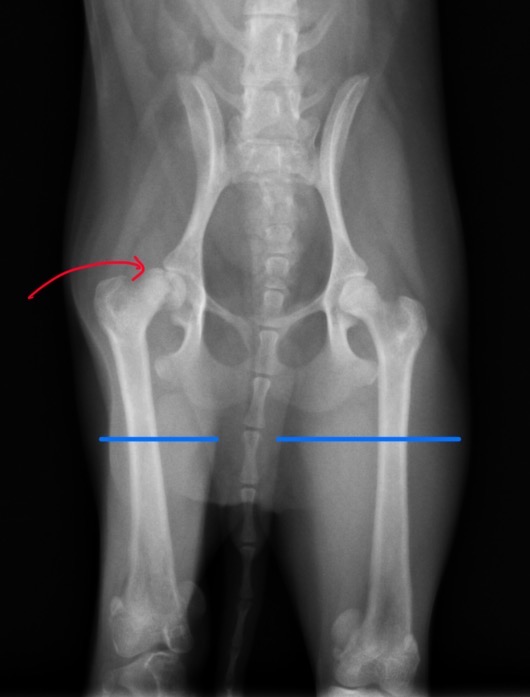

X線検査において、右大腿骨頭部のの剥離骨折が認められ(赤矢印)、背景にレッグカルベペルテス病(LCPD、無菌性虚血性大腿骨頭壊死症)(以下LCPD)の存在が疑われました。

また、右側の大腿部の筋萎縮が顕著に認められました(青線)。

これは廃用性萎縮といい、しばらくの間、股関節の痛みから右後ろ足をかばって生活していたためと考えられます。

術前X線 右大腿骨頭部の骨折(赤矢印)/ 大腿部の筋萎縮(青線)